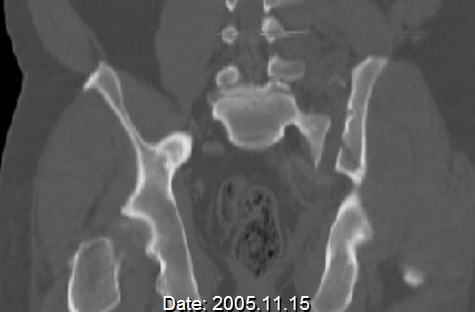

Hello gentlemen- Case is 52 YO male, fell out of treestand while deerhunting. He is 6 ft, approx. 260-275 lbs. Was hemodynamic unstable at local ER, sent to our Trauma center where circumferential pelvic binder placed and pt. stabilized with fluid, blood, and rewarming. Angiography not performed. An extraperitoneal bladder disruption was found, uro elected to treat non-operatively. Initial xray (not shown) demonstrated 5-7 cm wide at symphysis and SI joint. The first image attached is of CT once binder is in place. On post trauma day 5 the pt was taken to OR for ORIF of his iliac wing fracture and SI dislocation. The swelling/3rd spacing of fluid in the area of symphysis was profound, but quite acceptable posteriorly. Patient was prone for procedure, as I thought too difficult to fix the wing in lateral position. Of course the repair of wing was easy, but reduction of SI very demanding. The Floro images document the residual lack of reduction. That was the closest I could get it using 6mm joystick in wing, and clamp on sacrum and clamp through notch. The fixation was (initially) rigid. Anterior ex fix with supra-acetabular pins was placed due to condition of soft tissues, massive "beer-belly" overhanging the crest. Post trauma day ten patient's xray shows failure of posterior construct. Plan was to perform revision orif once soft tissues resolve considerably for full anrterior fixation and posterior fixation. However, while Im away for holiday (on Post trauma day 15), pt is developing septic clinical appearance, and trauma suspects pelvic abcess near symphysis and performs I and D - finds nothing but no primary closure performed. Posterior tissues/incision continue to look healthy. Now is post trauma day 17, pt is still tubed/on dopamine/and wbc still elevated, anterior incision still packed open. Clearly must get to bottom of possible sepsis, but then what? Thanks for you time - sorry for such lengthy clinical description. Thomas Schaller Kalamazoo, Michigan

Request for more images.. Axial and coronal recon (pt in binder.)

5. Your caudal iliosacral screw is/was in his spinal canal... it's low and posterior and the lateral fluoro image confirms this... a postop CT will show it (or it's trail at this point)... canal screws do not hold.

9. At this point, (if he's alive) get busy get a CT so you can understand what's happened, where the implants were, what fixation zones remain, remove the failed posterior implants, turn him supine, expose the symphysis and SI joint, reduce and clamp them both, fix them according to the CT info, close the wounds if clean, pack open if not, get another CT to assure adequate reductions and implant safety, treat his wound culture results with appropriate antibiotics, and nourish him.